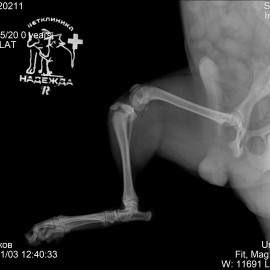

Снимок 1 до операции.